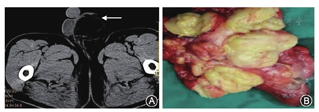

例2 54岁,因左侧阴囊复发性肿物进行性增大4年于2014年8月24日入院。既往于2007年8月、2009年8月先后在当地医院行阴囊肿物切除术,术后病理诊断均为阴囊脂肪瘤。此次入院查体:左侧阴囊内可扪及团块状肿物,11.0 cm×5.0 cm,平卧位不消失,透光试验(-)。B超检查示左侧阴囊上方探及一大小为11.8 cm×4.9 cm的强回声团块,边界清,内回声不均,其内未见明显血流信号,考虑脂肪瘤。阴囊CT平扫检查(图1A)示左侧阴囊内最大截面为5.2 cm×7.1 cm不规则形低密度灶,边界模糊不清,密度均匀,平均CT值为-104 Hu,增强扫描病灶呈轻度不均匀强化,左侧睾丸显示不清,考虑脂肪瘤或脂肪疝可能,腹部CT检查未见明显异常。硬膜外麻醉下行左侧阴囊肿物及左侧睾丸、附睾切除术。术中取左侧腹股沟区斜切口,向下至阴囊根部,长约10 cm,术中见肿物位于精索处,与精索粘连重,遂在内环口处高位结扎精索,完整切除左侧精索、睾丸、附睾及周围脂肪组织。术后病理检查:精索长6.5 cm,直径1.5 cm,一侧连有灰黄色分叶状肿物,肿物体积14.0 cm×11.0 cm×5.0 cm,切面灰黄,质软脆(图1B)。病理诊断:精索脂肪瘤样脂肪肉瘤,睾丸、附睾未见累及。随访27个月无瘤生存,无远处转移。

A.例1阴囊CT平扫示左侧阴囊内不规则形低密度灶,边界模糊不清,密度均匀(箭头所示); B.例2手术标本可见肿物灰黄色,呈分叶状,切面灰黄质软脆